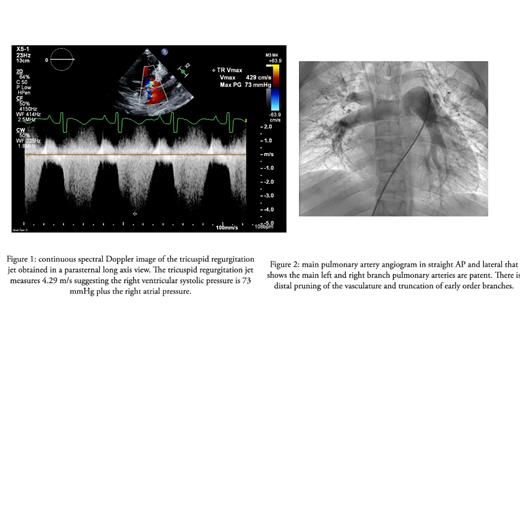

The patient is a 17-year-old female with a history of SCD, obstructive sleep apnea (OSA), nocturnal hypoxemia, and recurrent pain crises maintained on LTE every four weeks for the past seven years. She had previously failed hydroxyurea therapy. She underwent a tonsillectomy and adenoidectomy seven years ago to treat OSA. The patient had an echocardiogram five years ago, which showed normal biventricular function and tricuspid regurgitation jet velocity. Recently she presented to the emergency department with cough, shortness of breath, fever, diarrhea, and nausea lasting for three days. Initial assessment revealed elevated liver enzymes, elevated BNP, hyperbilirubinemia, hemoglobin of 9.5 g/dL, and oxygen saturations in the 80's. Echo revealed right ventricular dysfunction and right atrial and ventricular enlargement with a tricuspid regurgitation jet velocity of 4.29 m/s and estimated right ventricular systolic pressure 90% systemic, as seen in figure 1. The patient was admitted to the PICU under concern of pulmonary hypertension crisis. She underwent a right cardiac catheterization three days into her admission and was diagnosed with severe pulmonary hypertension with a mean pulmonary artery pressure of 49 mmHg. Pulmonary capillary wedge pressure was 11 mmHg, and pulmonary vascular resistance was calculated to be 18 wood units x m 2 with 20 PPM of nitric oxide and 80% FiO2 the PVR decreased to 11 woods units x m 2 (figure 2). CTA showed subsegmental thrombosis and vascular surgery was consulted for evaluation for endarterectomy, but they decided she was not a surgical candidate. She was initiated on anticoagulation therapy with enoxaparin, sildenafil, and bosentan.